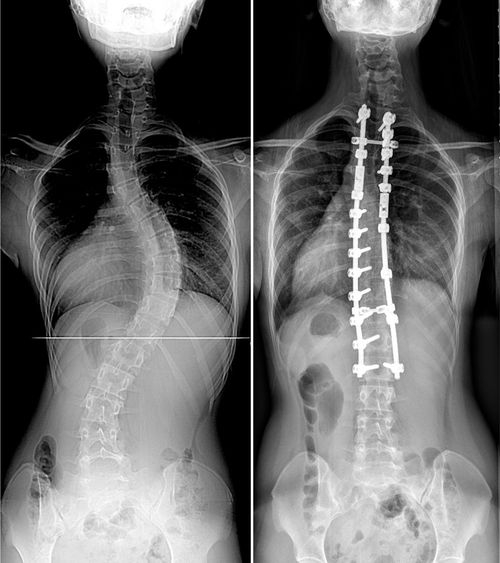

| 이중 흉추 청소년기 특발성 척추측만증 수술 전 후 수술당시 14세 여아사진으로 수술 전 상부흉추 36도, 하부흉추 62도의 측만증 소견. 수술 후 척추 측만증이 잘 교정되었고, 어깨 높이 균형도 양쪽이 대칭적으로 잘 유지 되고 있는 소견을 보이고 있다. |

인제대학교 상계백병원 척추센터 장동균 교수팀이 척추뼈가 어깨 쪽(상부 흉추)과 등 쪽(하부 흉추)에 두 번 휘어 있는 환자(이중 흉추 특발성 척추측만증) 57명을 대상으로 7년 이상 추적 관찰한 결과 수술 후 양쪽 어깨높이 균형을 잘 유지하기 위해선 상부 흉추가 경직이 있어 덜 교정되기 때문에, 상대적으로 하부 흉추를 덜 교정하는 것이 효과가 있었다고 밝혔다.

이중 흉추 특발성 측만증은 어깨 쪽 척추뼈(상부 흉추, 30도이상)와 등 쪽 척추뼈(하부 흉추, 40도이상) 등 두 개의 만곡 형태를 보인다. 상부 흉추 만곡의 유연성이 적어 좌측 어깨의 뒷면과 등 위쪽 근육(승모근)이 두드려져 보이는 특징을 가진다.